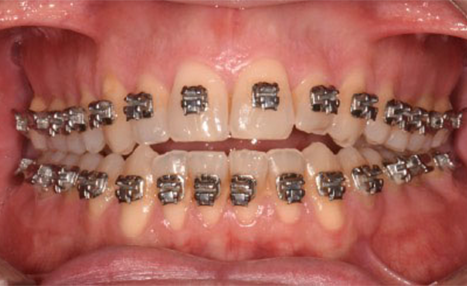

A 38-year-old male patient sought orthodontic treatment with both functional and esthetic concerns. His main complaints included the appearance of an inverted smile arc, reduced incisor display, and a general lack of harmony in his smile.

The extraoral examination revealed a long facial type with an increased lower facial third, nasolabial folds accentuated by insufficient midface support, and broad buccal corridors due to maxillary compression. Intraoral analysis showed a posterior crossbite, negative torque on posterior teeth, and an altered occlusal balance. Radiographic and cephalometric evaluation confirmed the clinical findings, with an increased mandibularplane angle and mandibular posterior rotation. This rotation contributed to a convexity of +4 mm, although the underlying problem was a retruded maxilla with insufficient midface support. Vertical facial height was also increased. Importantly, the temporomandibular joint evaluation showed a posterior condylar position with intact cortical bone, no pain, and no joint sounds.

(Images: Intraoral Initial)